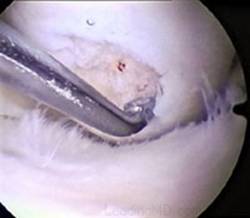

Dupa indepartarea cu succes a stratului de cartilaj calcifiat, o andrea este folosita pentru a face mai multe gauri mici (mirofracturi) in osul expus al defectului condral aflate la distanta de 1-2 mm. Trebuie lasata o punte de oase potrivita intre gauri. Tehnica de microfracturi are numeroase avantaje fata de foraj. Mai intai de toate, creaza o leziune termala mai mica. Mai mult, cu microfracturi chirurgul este capabil sa intre in zonele dificile ale suprafetei articulare cu un control mai bun asupra adancimii de patrundere. La finalizarea microfracturii, o suprafata aspra este generata pentru aderenta cheagului de sange care contine celule mezenchimale nediferentiate de la osul subcondral. Trebuie avut grija ca cele mai marginase parti ale leziuni sa fie patrunse de andrea pentru a ajuta la vindecarea tesutului reparator la imprejmuirea suprafetei articulare. Odata ce microfractura este finalizata, pompa artroscopica este oprita pentru a se asigura ca sangerarea maduvei curge din gaurile mici umpland defectul.[54]

Fig.25.a. Debridarea. Fig.25.b. Microfracturare.

Fig.27. Microfracturi.

Fig.28. Sange din microfracturi.